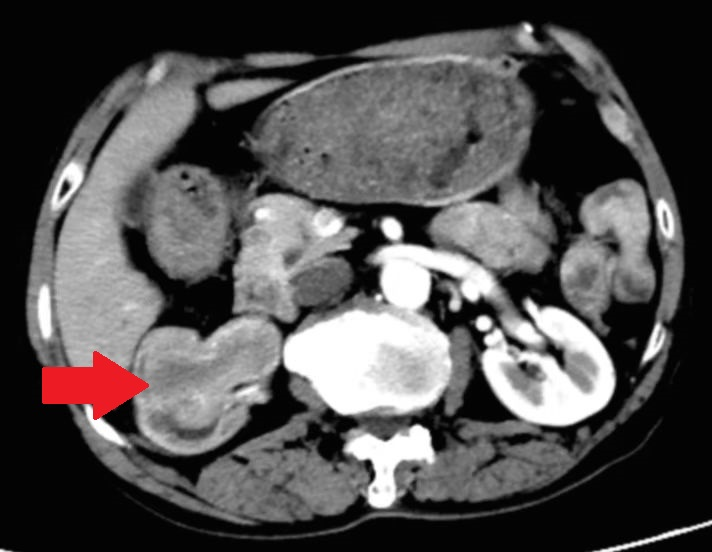

经过详细的增强CT检查,医生发现该患者的右肾下极、肾盂及右输尿管上段出现了占位性病变,初步考虑为恶性肿瘤,肿瘤最大层面达到5公分。这一发现让患者和家属倍感焦虑,但在泌尿外科团队的精心医治下,患者最终得到了有效的治疗。